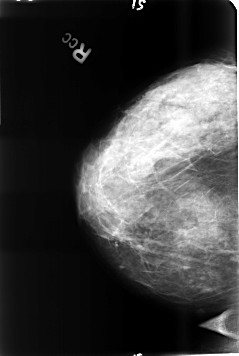

B_3456_1.RIGHT_CC

RIGHT_CC LINES 4616 PIXELS_PER_LINE 3104 BITS_PER_PIXEL 12 RESOLUTION 50 NON_OVERLAY